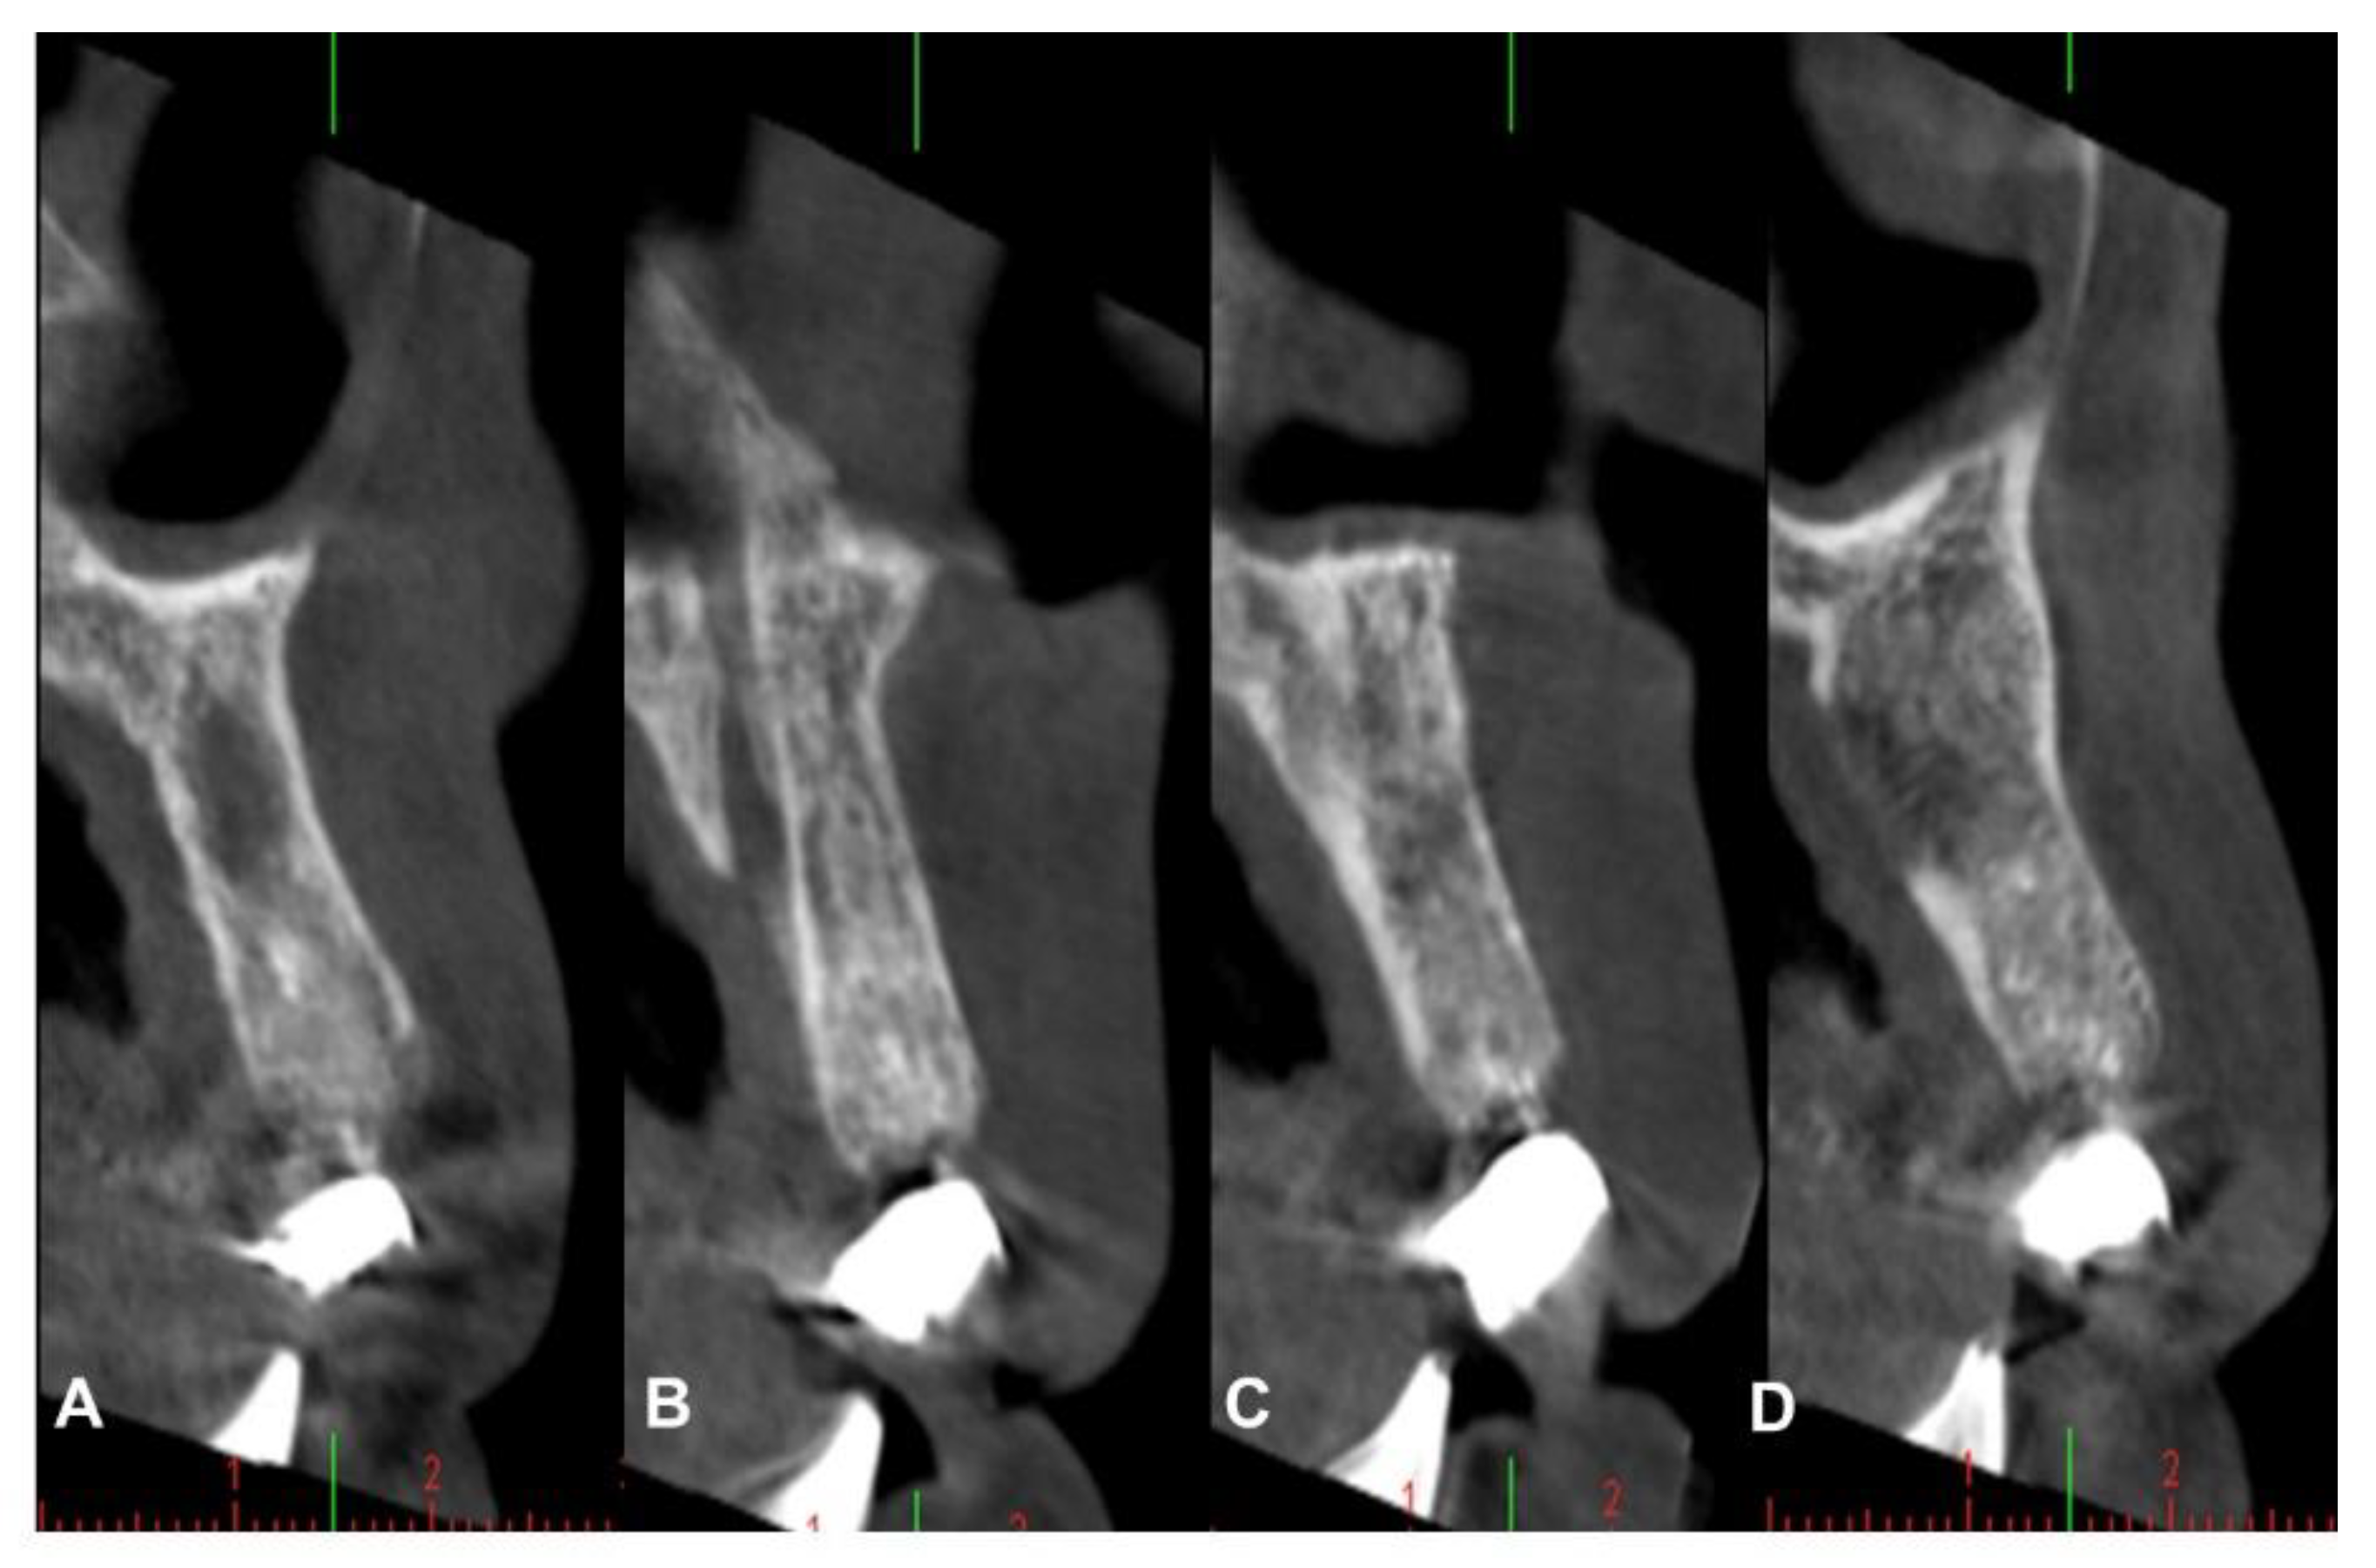

4.2. Patient No. 2

4.3. Patient No. 3

4.4. Patient No.4

4.5. Patient No.5